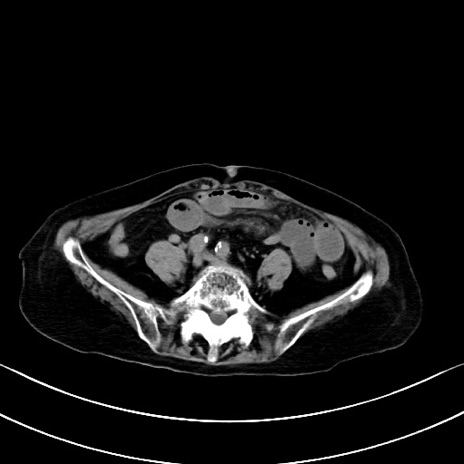

横断像